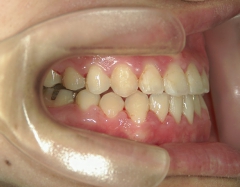

矯正歯科 治療後矯正歯科 全顎ワイヤー矯正 治療後矯正歯科(全顎ワイヤー矯正)治療後

主訴:受け口(反対咬合)を治したい

no.31_7964_治療後_右 .JPGno.31_7964_治療後_正面 .JPGno.31_7964_治療後_左.JPG